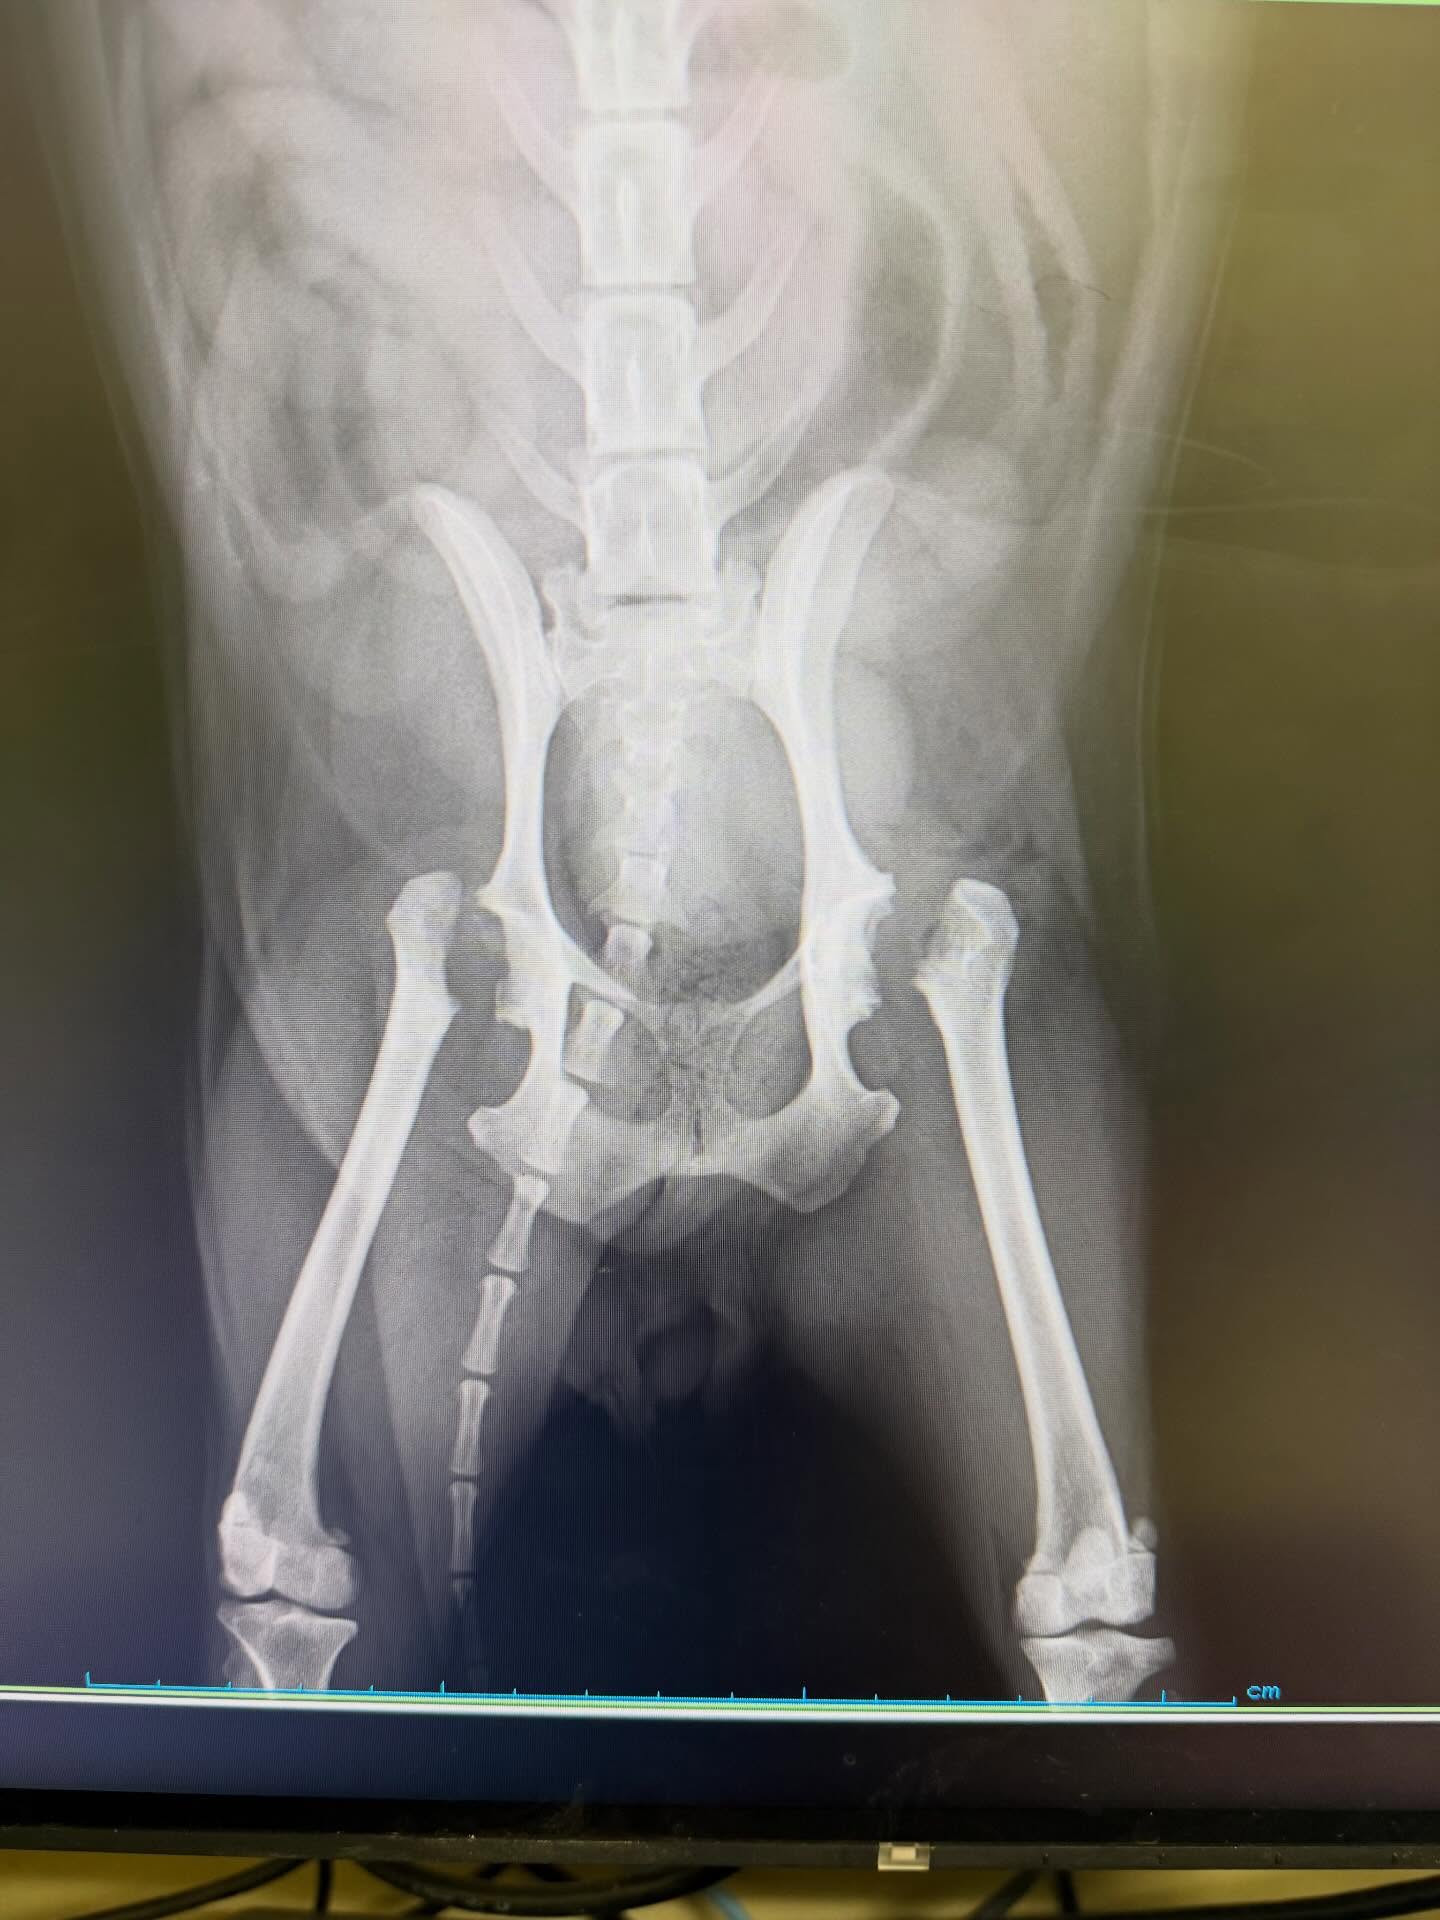

“股関節の手術”

過去に片方の股関節を手術したワンちゃん。反対側の股関節も関節炎が進行し、変形してきて、しかも亜脱臼の兆候も出てきていたため、反対側の手術を行いました。

人間でも股関節の病気は多く、中高齢になると発症することが多い病気。人間では人工股関節の手術も進化し、動物でも人工股関節の手術は高度獣医療施設で可能ですが、費用も高額。ですので、大腿骨頭骨頚部切除術という太ももの骨の頭を切る手術が一般的です(画像参照)。特に、消炎鎮痛剤による内科的な維持をすることもありますが、薬を飲んでも痛みが出てきたり、長期使用による腎臓負担のリスクや、体重が重い子ほど将来的に進行する可能性が高く、予防的に手術する場合があります。